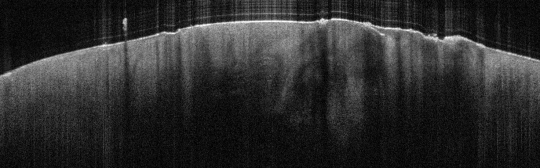

VA111: Left Cheek Superior, Squamous Cell Carcinoma, Invasive

- Arrow denotes point at which collagen texture begins to diminish before becoming merged with the texture of squamous cells